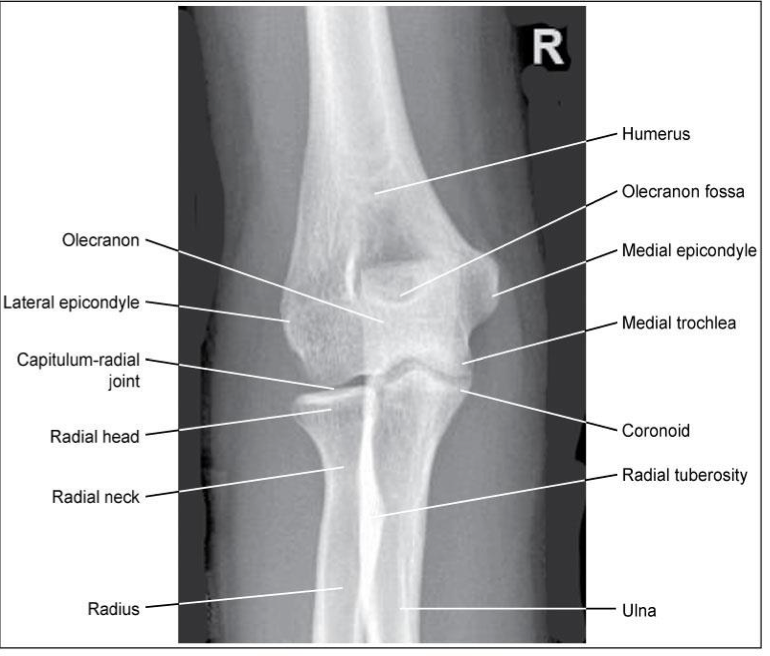

AP Elbow

Patient Position

▪ Sitting at end or side of table

▪ Arm fully extended; hand supinated; entire upper limb at same height

▪ If hand is not supinated: radius & ulna are crossed

Part Position

▪ Place elbow on IR in a true AP – Humeral epicondyles equal distances from the

IR

▪ Patient may need to lean laterally

CR

▪ Perpendicular to elbow joint

Collimation

▪ To include distal humerus and proximal radius/ulna

Evaluation Criteria for AP elbow

• Radial head, neck& tuberosity are slightly (approx. 0.6 cm) superimposed over the proximal ulna

Medial rotation causes too much superimposition

Lateral rotation causes too little superimposition

• Radial tuberosity in profile medially

• Olecranon located in the olecranon fossa

• No rotation of humeral epicondyles